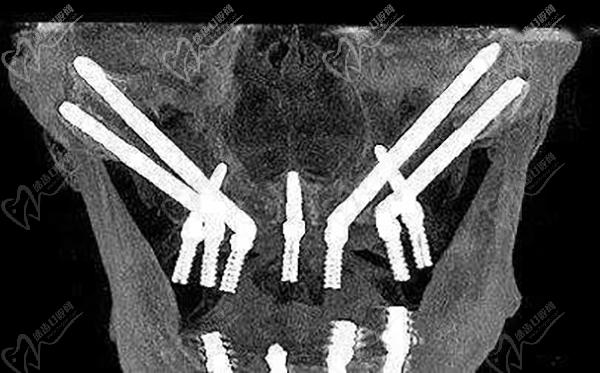

4、西安滿口穿顴穿翼種植牙價格:18萬-25萬元起

適合于:高齡疑難全口無牙頜種植、牙槽骨重度萎縮、骨量不足植骨難度大的種牙患者。

能實現(xiàn)當(dāng)天種牙當(dāng)天戴牙的便捷服務(wù),解決了高難度種牙患者的種牙訴求,手術(shù)微創(chuàng)舒適,種植牙非常堅固耐用,因為是將兩個超長植體植入了顴骨或翼板,非常牢靠。

西安滿口穿顴穿翼種植牙價格:18萬-25萬元起